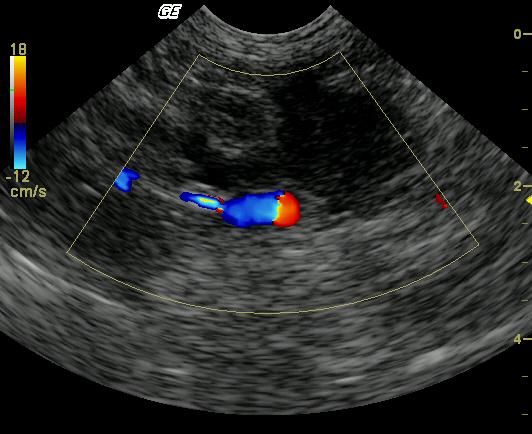

This 14-year-old FS DSH was presented for lethargy and vomiting. The physical exam revealed icterus, dehydration, and emaciation with thickened bowel loops and irregularly shaped kidneys on palpation. The CBC revealed only elevated absolute monocytosis while blood chemistry results revealed a markedly elevated ALT, markedly elevated lipase, and markedly elevated total bilirubin, with moderate azotemia, hyperglycemia and low T4. Urinalysis findings included 3+ bilirubinuria, spec gravity of 1.032, and cocci bacteria.